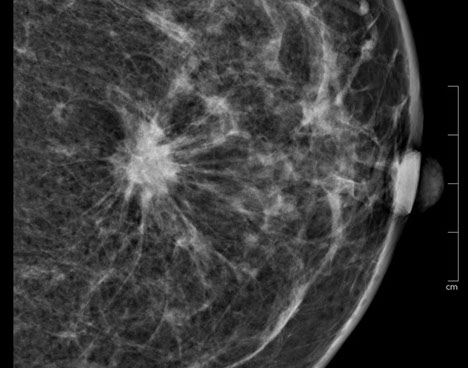

3.  Exaktere Bildanalyse – sicherere Diagnose

Durch die höhere Kontrastauflösung bei einem höheren Kontrast-Rausch-Verhältnis wird die Erkennungsrate von malignitätsverdächtigen Veränderungen deutlich verbessert. Der Radiologe kann auf hochauflösenden 5 MP-Monitoren die Dichte, Form und Kontur von Gewebearealen wesentlich exakter differenzieren und so gutartige von bösartigen Herdbefunden sicherer unterscheiden. Im Speziellen sind Mikroverkalkungen auch bei der dichten Brust besser zu analysieren.

Die Diagnosesicherheit und Möglichkeit einer Brustkrebsfrüherkennung durch die Mammographie, hängt von der Dichte des Brustdrüsengewebes ab. Einteilung der Dichtegrade wurde vom American College of Radiology (ACR) übernommen.

Bei einem Dichtegrad 3 sinkt die Sensivität der Mammographie deutlich, bei Dichtegrad 4 liegt sie unter 50 %. Durch gleichzeitigen Einsatz der Ultraschalluntersuchung wird die Sicherheit in der Diagnoseerstellung jedoch wieder auf

ca. 90 % angehoben.

40 % der Mammakarzinome weisen Mikroverkalkungen auf. Mikrokalzifikationen sind auch bei sehr dichtem Brustgewebe immer sichtbar. Eine Mammographie sollte daher ab dem 40. Lebensjahr die primäre Untersuchungsmethode sein.